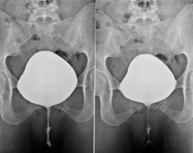

- Voiding Cystourethrography (VCUG)

Serial voiding cystourethrography involves radiological imaging to assess the anatomy and function of the urethra and bladder with the administration of iodinated contrast through a bladder catheter.

- Urethrocystography (Urethro-CG)

Retrograde-minctional urethrocystrography involves radiological imaging to assess the anatomy and function of the bladder and urethra. Contrast material is applied through a small catheter placed in the urethra and images are obtained during the filling and emptying of the bladder.